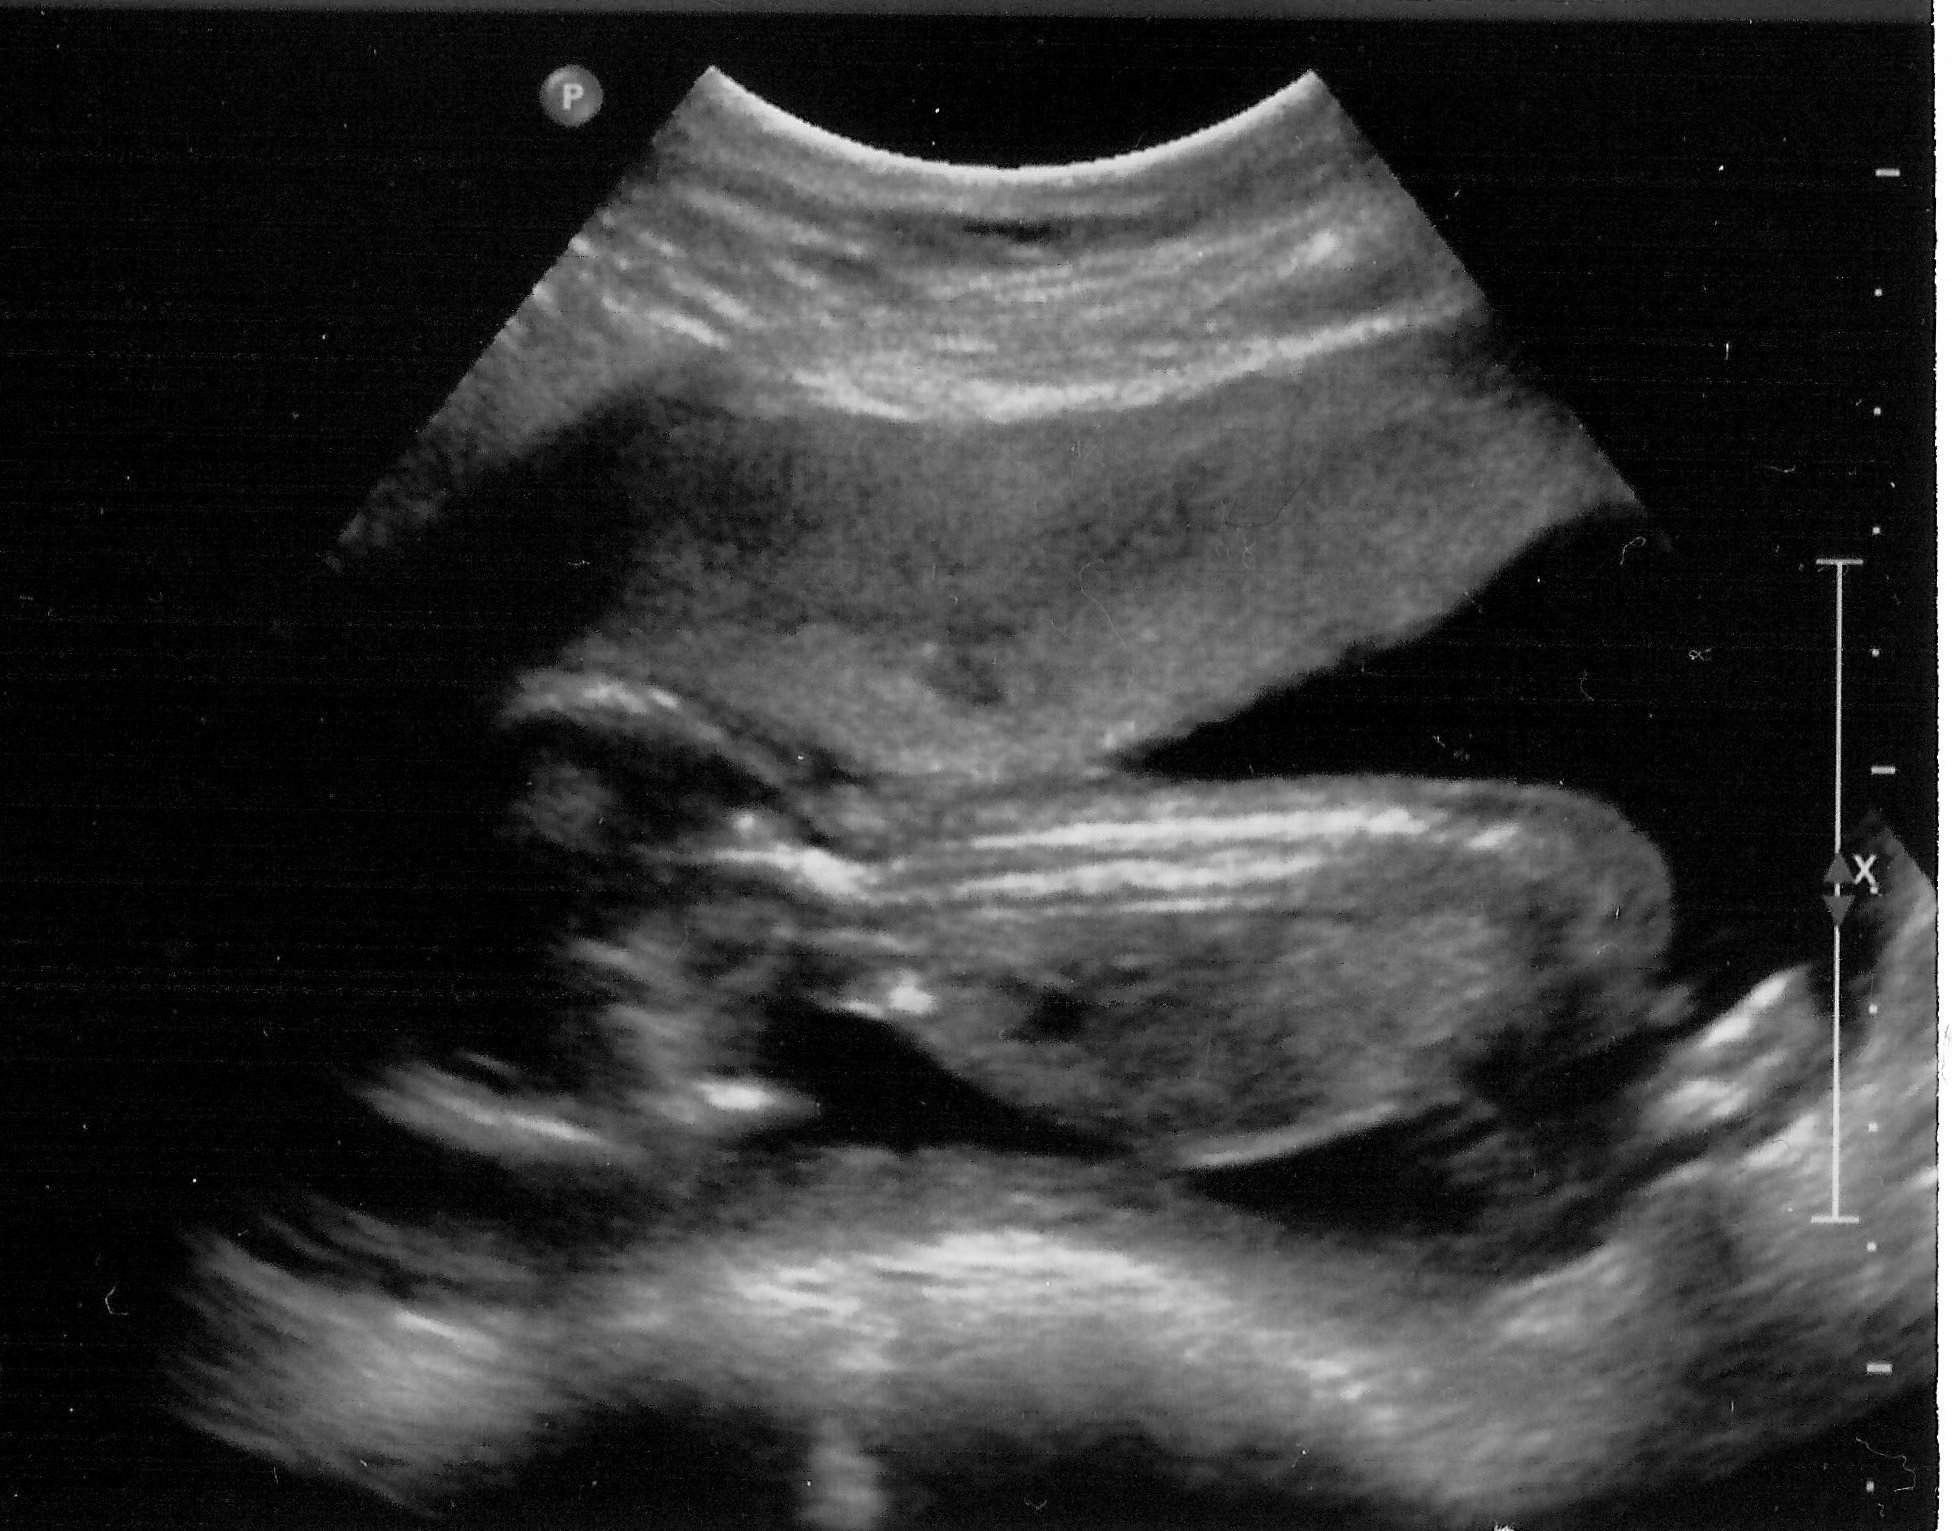

A grainy and blurry black and white photo of a baby in utero

Baby is facing down, head on the left, bottom and legs on the right.

We’re absolutely overjoyed at this fantastic news — it’s been so difficult keeping it quiet. All was well at the scan, and Baby Godbolt is due in mid-July. I can’t wait!